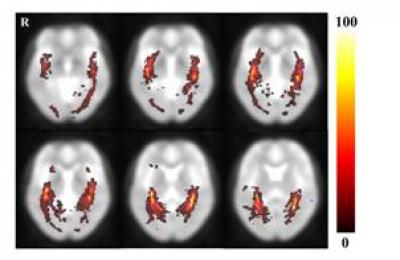

image: This image shows the results of the optic radiation probability pathway map in healthy subjects. The hot color scale indicates the proportional degree of overlap for all subjects and the probability of a voxel being part of the optic radiation fiber tract pathway. view more

The optic radiation is a dense fiber tract that emerges from the lateral geniculate nucleus and continues to the occipital visual cortex. Especially, the optic radiation is an important fiber structure that conveys visual information from the lateral geniculate nucleus to the primary visual cortex in the occipital lobe. Current studies have focused on the anatomical characteristics of optic radiation fiber tracts in individual brains and on comparisons of the anatomical characteristics of the optic radiation fiber tracts between patient and control groups. Therefore, no diffusion tensor tractography studies of the volumetric information of optic radiation have been conducted without individual brain structure variation. To attain the volumetric information of the optic radiation in normal human brains, Dr. Cheol-Pyo Hong and coworkers from Korea Research Institute of Standards and Science (KRISS) performed diffusion tensor imaging examination in 13 healthy volunteers. Their results showed that the measured optic radiation fiber tract volume was a range of about 0.16% and that the fractional anisotropy value was about 0.53. Moreover, the optic radiation probability fiber pathway that was determined with diffusion tensor tractography-based group mapping was able to detect the location relatively accurately. The methods and results from Dr. Cheol-Pyo Hong and coworkers are helpful in the study of optic radiation fiber tract information, which has been reported in the Neural Regeneration Research (Vol. 9, No. 3, 2014).